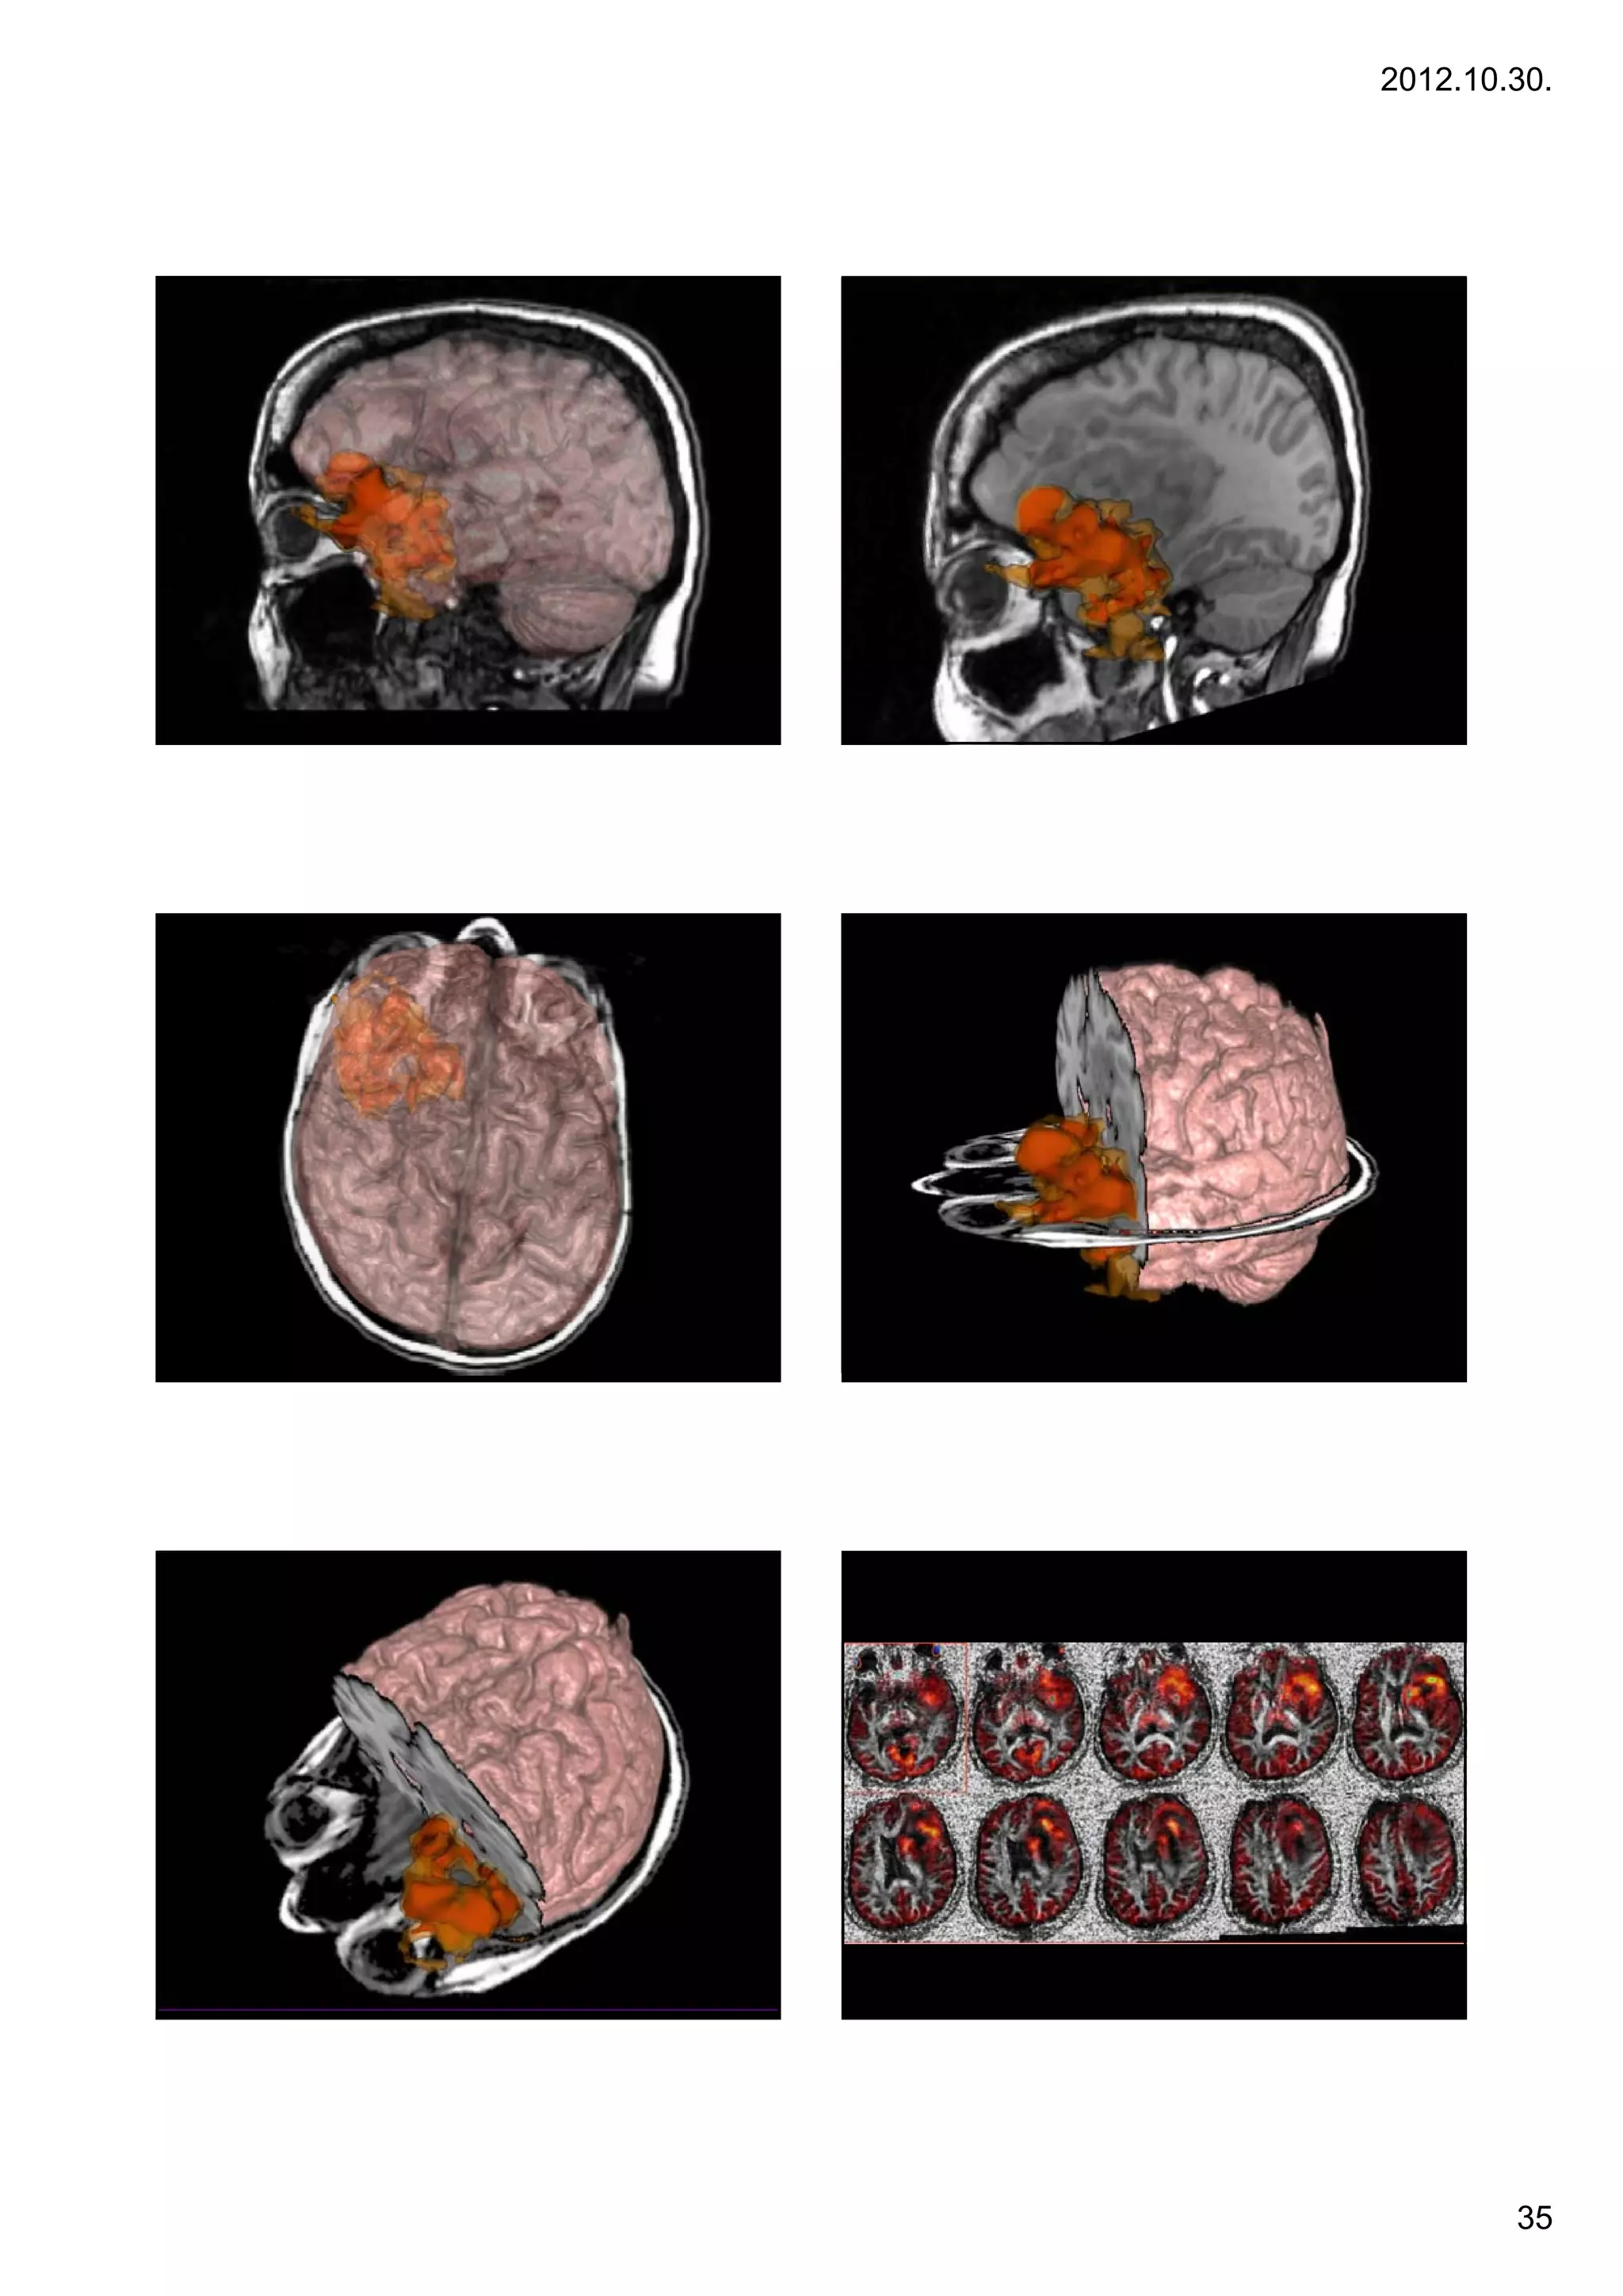

PET imaging                 PET imaging

• fdsfsd                 • FDG: F-18 fluorodeoxyglucose positron

emission tomography (FDG-PET)

– Glucose metabolism, perfusion

– Necrosis: no FDG

• C11 – methionine

– Membrane turnover

– Cellular metabolism, tumor activity

34

FDG – MRI – DTI fusions